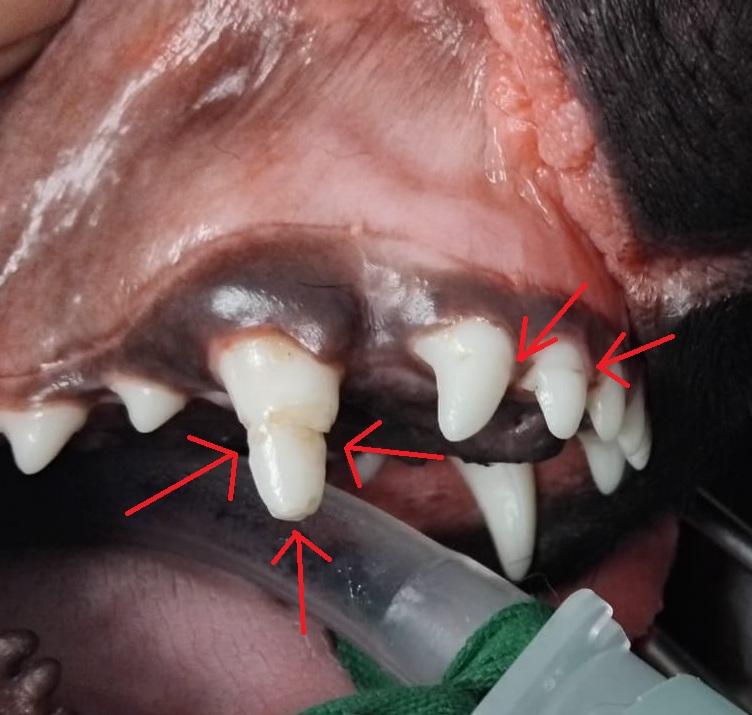

C'est le cas de Alphonse, qui nous a été présenté en vue de sa castration à l'âge de 9 mois, et dont l'anomalie dentaire est une découverte fortuite de la consultation.

L'origine de l'anomalie n'est pas connue. Les deux incisives adjacentes au croc étant également atteintes, il est probable qu'il s'agisse d'une malformation de l'émail, probalement traumatique, quand ces dents étaient au stade de bourgeon dentaire.

La radiographie est indispensable dans ce cas pour vérifier la meilleure conduite à tenir :